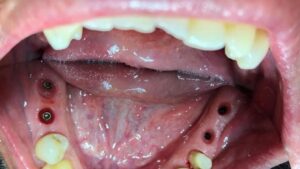

تقنيات حديثة للزراعة

تضيف اجهزه البانوراما الداخلية واجهزة التصوير ثلاثية الأبعاد بعدًا آخر لتقنية الزرع من خلال صورها الدقيقة للفك والأسنان. هذه الدقة ضرورية لتخطيط ووضع الغرسات. يوفر تقييمًا دقيقًا للبنى التشريحيه مثل الأعصاب وجذور الأسنان والجيوب الفكية ومعرفة طبيعة العظم وكثافة وما إلى ذلك ، مما يمنع أي احتمال للفشل الذي يحدث بسبب التشخيص الخاطئ. تم تجهيز مراكز الزرع لدينا بهذه الآلات المتطورة ، مما يمكننا من تنفيذ كل حالة من حالات الزرع بدقه عاليه وأعلى درجات النجاح.